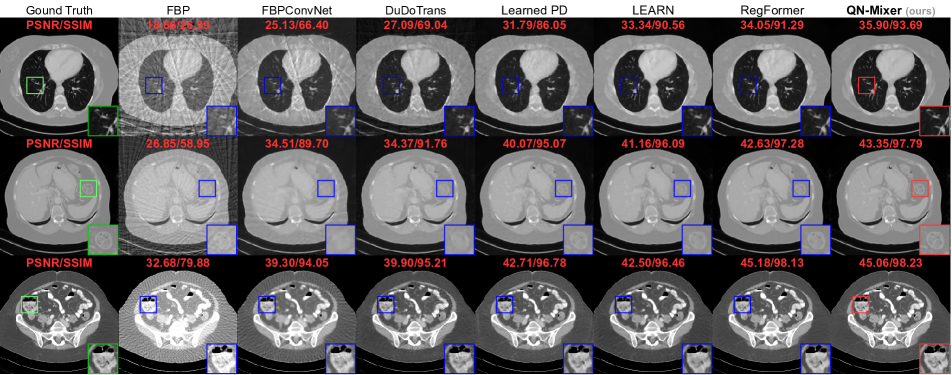

Figure 1: CT Reconstruction with 32 views of State-of-the-Art Methods. Comparative analysis with post-processing and first-order unrolling networks highlights QN-Mixer’s superiority in artifact removal, training time, and data efficiency.

Figure 4: Visual comparison on AAPM. From top to bottom: the results under the following conditions: first (nv=32,N1)subscript𝑛𝑣32subscript𝑁1(n_{v}=32,N_{1}), second (nv=64,N1)subscript𝑛𝑣64subscript𝑁1(n_{v}=64,N_{1}), third (nv=32,N0)subscript𝑛𝑣32subscript𝑁0(n_{v}=32,N_{0}). The last row presents out-of-distribution (OOD) results with a randomly overlaid circle on a test image. The display window is set to [1000,800]1000800\left[-1000,800\right] HU.

Quantitative comparison.  We compared our model with state-of-the-art baselines on two public datasets. For AAPM, models were trained and tested across three projection views (nv{32,64,128}subscript𝑛𝑣3264128n_{v}\in\{32,64,128\}) and three noise levels, namely no noise N0=0subscript𝑁00N_{0}=0, low noise N1=106subscript𝑁1superscript106N_{1}=10^{6}, and high noise N2=5×105subscript𝑁25superscript105N_{2}=5\times 10^{5} (see Tab. 1). For DeepLesion, models were trained and tested on the same three projection views and a noise level of N1=106subscript𝑁1superscript106N_{1}=10^{6} (see Tab. 2). Visual results are provided in Fig. 4 (AAPM) and Fig. 5 (DeepLesion). Impressively, our method achieves state-of-the-art results on DeepLesion across all projection views. It outperforms the second-best baseline, RegFormer, with an average improvements of +2.232.23+2.23 dB in PSNR and +1.021.02+1.02% in SSIM. On AAPM without noise, we achieve state-of-the-art results across all projection views and improve the second best by an average +1.651.65+1.65 dB and +0.58%percent0.58+0.58\%. In the presence of low noise, QN-Mixer achieves state-of-the-art results performance in all cases except nv=128subscript𝑛𝑣128n_{v}=128 with 0.110.11-0.11 dB and shows an average improvements of +0.330.33+0.33 dB and +0.350.35+0.35% over RegFormer. With high noise, our method performs nearly on par in nv=32subscript𝑛𝑣32n_{v}=32 (0.020.02-0.02 dB and 0.290.29-0.29%), achieves state-of-the-art in nv=64subscript𝑛𝑣64n_{v}=64 (+0.20.2+0.2 dB and +0.080.08+0.08%), and competes closely in nv=128subscript𝑛𝑣128n_{v}=128 (0.010.01-0.01 dB and +0.080.08+0.08%). As noise increases, we attribute the decline in improvement to the compressed gradient information in the latent BFGS, influenced by sinogram changes, and the utilization of the FBP algorithm instead of the pseudo-inverse.

Visual comparison.  As it can be seen on Fig. 4 and Fig. 5, FBPConvNet and DuDoTrans exhibit noticeable blurry images with severe artifacts when nv=32subscript𝑛𝑣32n_{v}=32. While Learned PD and LEARN show satisfactory performance, they struggle with intricate details, like in the liver and spine. In contrast, RegFormer produces high-quality images but faces challenges in generalizing to OOD data. QN-Mixer excels in producing high-quality images with fine details, even under challenging conditions such as nv=32subscript𝑛𝑣32n_{v}=32 views and OOD data.